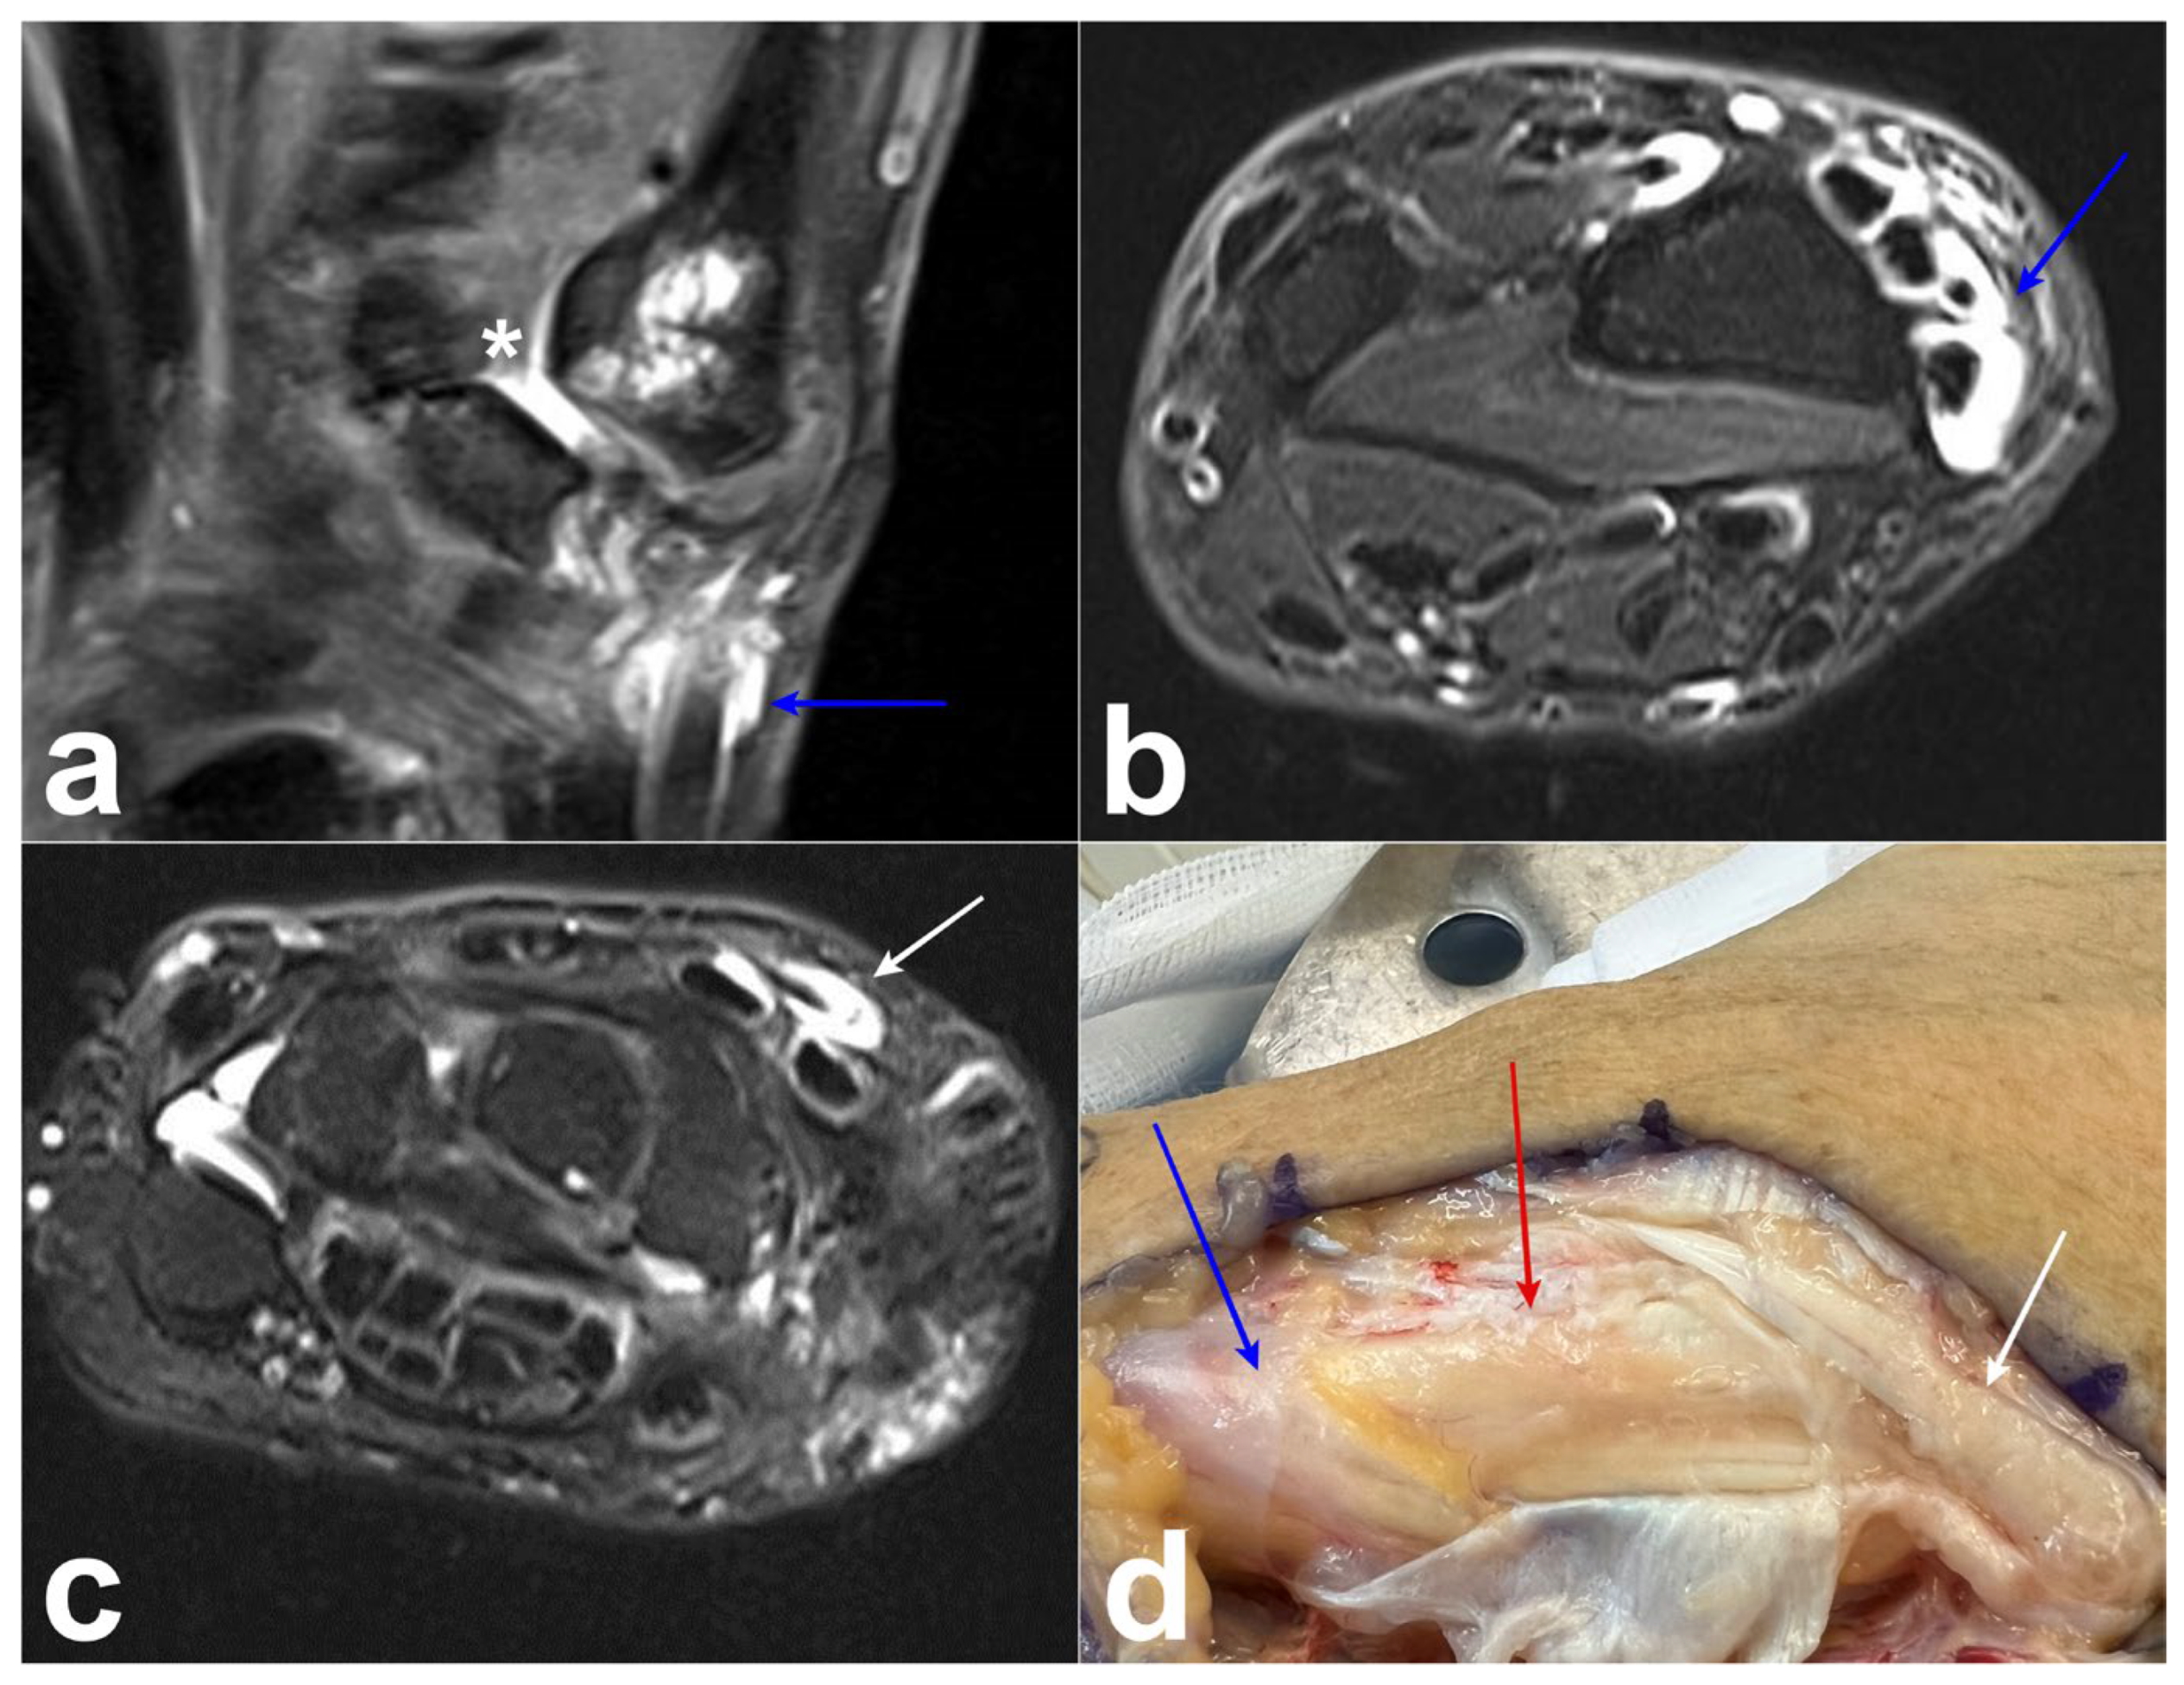

A 67-year-old woman with rheumatoid arthritis and a history of trapeziectomy 2 years before presentation presented to our clinic with swelling and pain in the dorsoradial aspect of the left wrist. MRI demonstrated the presence of a conflict between the scaphoid and the first metacarpal, and confirmed the diagnosis of DIT, as well as tenosynovitis of the abductor pollicis longus (APL) and extensor pollicis brevis (EPB) tendons (Figure 6a–c). Because of failed primary conservative treatment consisting of splinting and non-steroidal anti-inflammatory drugs (NSAID), we decided to proceed with surgery. The perioperative findings confirmed that the conflict between the first metacarpal and scaphoid caused tenosynovitis, which spread to the first, second, and third compartments (Figure 6d). The surgery consisted of the extended teno-synovectomy of every concerned tendon, joint synovectomy, interposition ligamentoplasty with the palmaris longus (PL) tendon anchovy, and the subcutaneous transposition of the EPL tendon. After six months, we noticed that the DIT had disappeared, the ultrasound was normal, and the patient was free of pain.

Figure 6. Case 4. (a) Conflict between the first metacarpal and scaphoid (asterisk) and tenosynovitis around the APL tendon (arrow) on MRI (coronal T2-weighted turbo spin-echo with fat saturation and dual-phase acquisition). (b,c) Tenosynovitis of the EPL, ECRB, and ECRL tendons associated with tenosynovitis of the APL and EPB tendons on MRI (axial T2-weighted turbo spin echo with Dixon fat suppression). (d) Preoperative photograph showing tenosynovitis of the EPL (white arrow), ECRB, ECRL (red arrow), and APL (blue arrow).